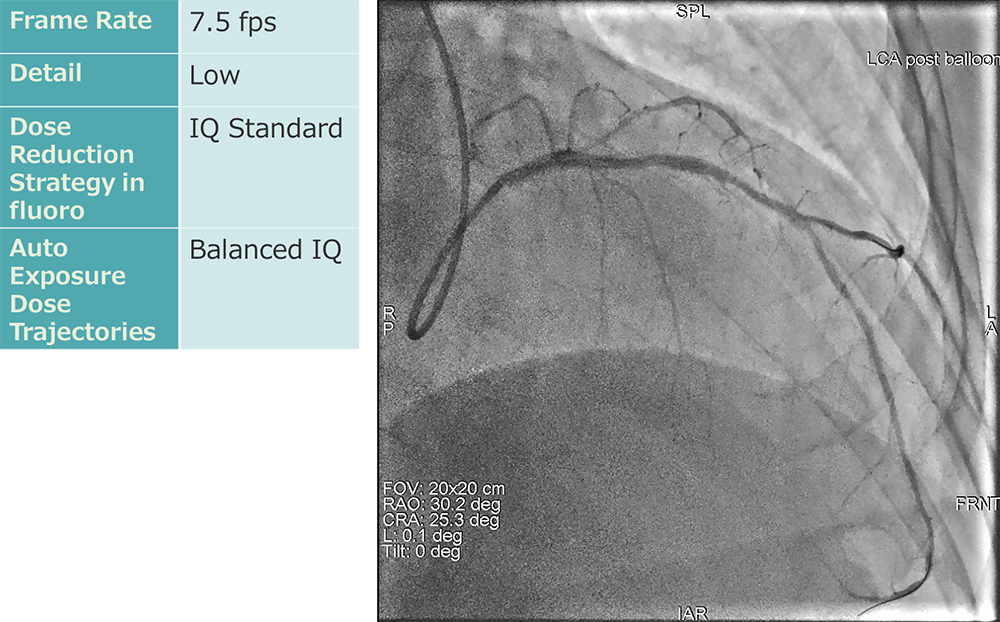

② 冠動脈領域

冠動脈領域の検査・治療における透視条件は、フレームレート7.5fpsに設定しています。当院での透視条件設定を表に示します。この設定条件において、指頭型電離箱を用いて臨床と同じ配置での線量率を計測しました。FOV20cm、SID100cm、PMMA20cmでの患者照射基準点における透視線量率は6.74mGy/minでした。既存の他社装置の場合では、透視フレームレート設定を7.5fpsに小さくすると残像が目立つ傾向が強いため、稼働前に滑らかな動作とノイズのバランスの良い動画の設定を行っています。線量を抑えた設定にも関わらず、透視画像にて既存他装置に引けを取らない視認性を実現しています。

IGS620_kurume_05.jpg

冠動脈撮影条件:7.5fpsでも視認性が保たれている